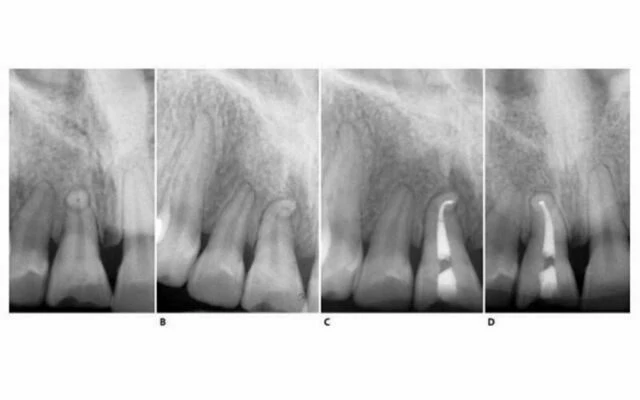

X-quang theo chiều gần xa

Hình 11.25. A. X-quang theo chiều gần xa  hình ảnh  răng cửa giữa trên. B. Sơ đồ biểu thị hình ảnh răng trước đó. C. Mũi khoan kim cương tròn sau khi hoàn thành pha xuyên qua. D. Sơ đồ của răng lúc này.

Phim X-quang điều trị của răng cửa giữa hàm trên bên phải

Hình 5.41. A. Phim X-quang trước điều trị của răng cửa giữa hàm trên bên phải. Lỗ chóp nằm trên cùng một mặt phẳng trên đường đi của tia X: nó có thể đối diện với mặt trong hoặc mặt ngoài. B. Phim X-quang thứ hai chụp theo hướng gần-xa cho thấy đoạn cong đối diện với mặt ngoài. Việc điều trị tủy được hoàn tất, giữ nguyên góc chụp cho phép nhìn thấy được điểm cuối cùng trên X-quang của ống tủy. C. Phim sau điều trị. Lưu ý rằng chỉ với góc chụp này mới thấy được hình ảnh tổn thương nhỏ tại chóp chân răng. D. Phim sau điều trị được chụp theo tiêu chuẩn hình chiếu. Lưu ý rằng vật liệu trám ống tủy dường như bị ngắn đi chừng 2mm và tổn thương cũng đã lành.